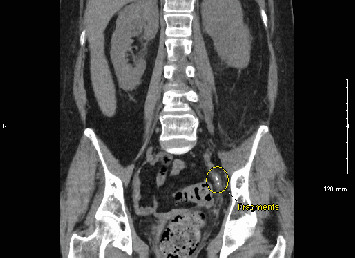

尿脓毒症是一种源自泌尿道的严重感染,可能危及生命。我们报告了一位56岁的女性患者,她在15天内两次出现尿脓毒症,每次发作都发生在支架移除后不久。输尿管镜下支架置入治疗左侧远端输尿管12毫米结石。尽管在影像学检查未发现结石残留后才取出支架,但不久后脓毒症发生,导致再次输尿管镜检查和支架置入。在第二次支架移除之前,影像学再次证实没有结石存在,但在第二次支架移除后,她再次出现败血症。两例败血症住院期间的进一步影像学检查显示结石碎片和肾积水,这在办公室评估中被遗漏。这个病例强调需要更有效的成像技术来检测残留的结石。输尿管镜下输尿管结石治疗后放置支架的决定也应仔细考虑,即使是低风险患者,以减少感染风险。

Urosepsis, a severe infection originating from the urinary tract, can be life-threatening. We present the case of a 56-year-old female who developed urosepsis twice within 15 days, each episode occurring shortly after stent removal. Ureteroscopy with stent placement was initially performed to treat a 12-mm stone in the distal left ureter. Although the stent was removed only after imaging showed no residual stones, sepsis developed shortly after, leading to another ureteroscopy and stent placement. Before the removal of the second stent, imaging again confirmed no stones were present, yet she experienced sepsis once more following the second stent removal. Further imaging studies during hospital admission for both episodes of sepsis revealed stone fragments and hydronephrosis which were missed during office evaluations. This case highlights the need for more effective imaging techniques to detect residual stones. The decision to place a stent after ureteroscopy for ureteral stone treatment should also be carefully considered, even for low-risk patients, to reduce infection risk.